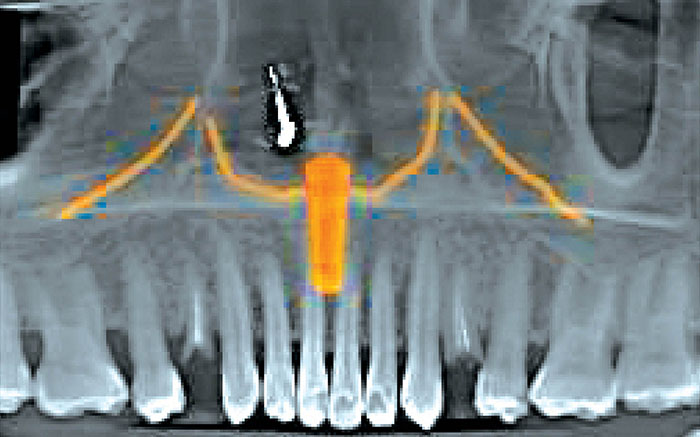

On examination, root stumps were noted on both right and left upper arch and the patient was expecting effective solution. After a thorough discussion of treatment options, including dental implants, the patient opted for implant therapy. Following a detailed consultation, a well-planned implant procedure was done and now the patient smiles with renewed ease and assurance.

Using cone-beam CT scans, Dr. Hemalatha ensures precise planning and minimally invasive implant surgery — ideal for patients requiring bone grafts or sinus lifts. Dental implants — titanium or zirconia — are securely anchored in the jaw and support prosthetics such as crowns or dentures, restoring both function and aesthetics.